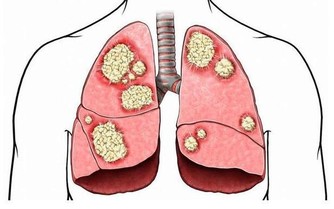

調查結果顯示,吸煙或者吃烤肉等在體內聚集的強致癌物質多環芳香烴,

在喝紅酒後會顯著降低,特別是喝了100%葡萄原汁的紅葡萄酒。

研究人員對吸煙者進行了試驗,讓他們在4天內連續每天喝200ml紅酒,

並測定喝紅酒前後尿液中多環芳香烴的代謝產物1-羥基芘含量。

結果發現,吸煙6小時後喝杯紅酒,人體血液內1-羥基芘會經尿液大量排出;如果不喝紅酒,1-羥基芘排出很少。